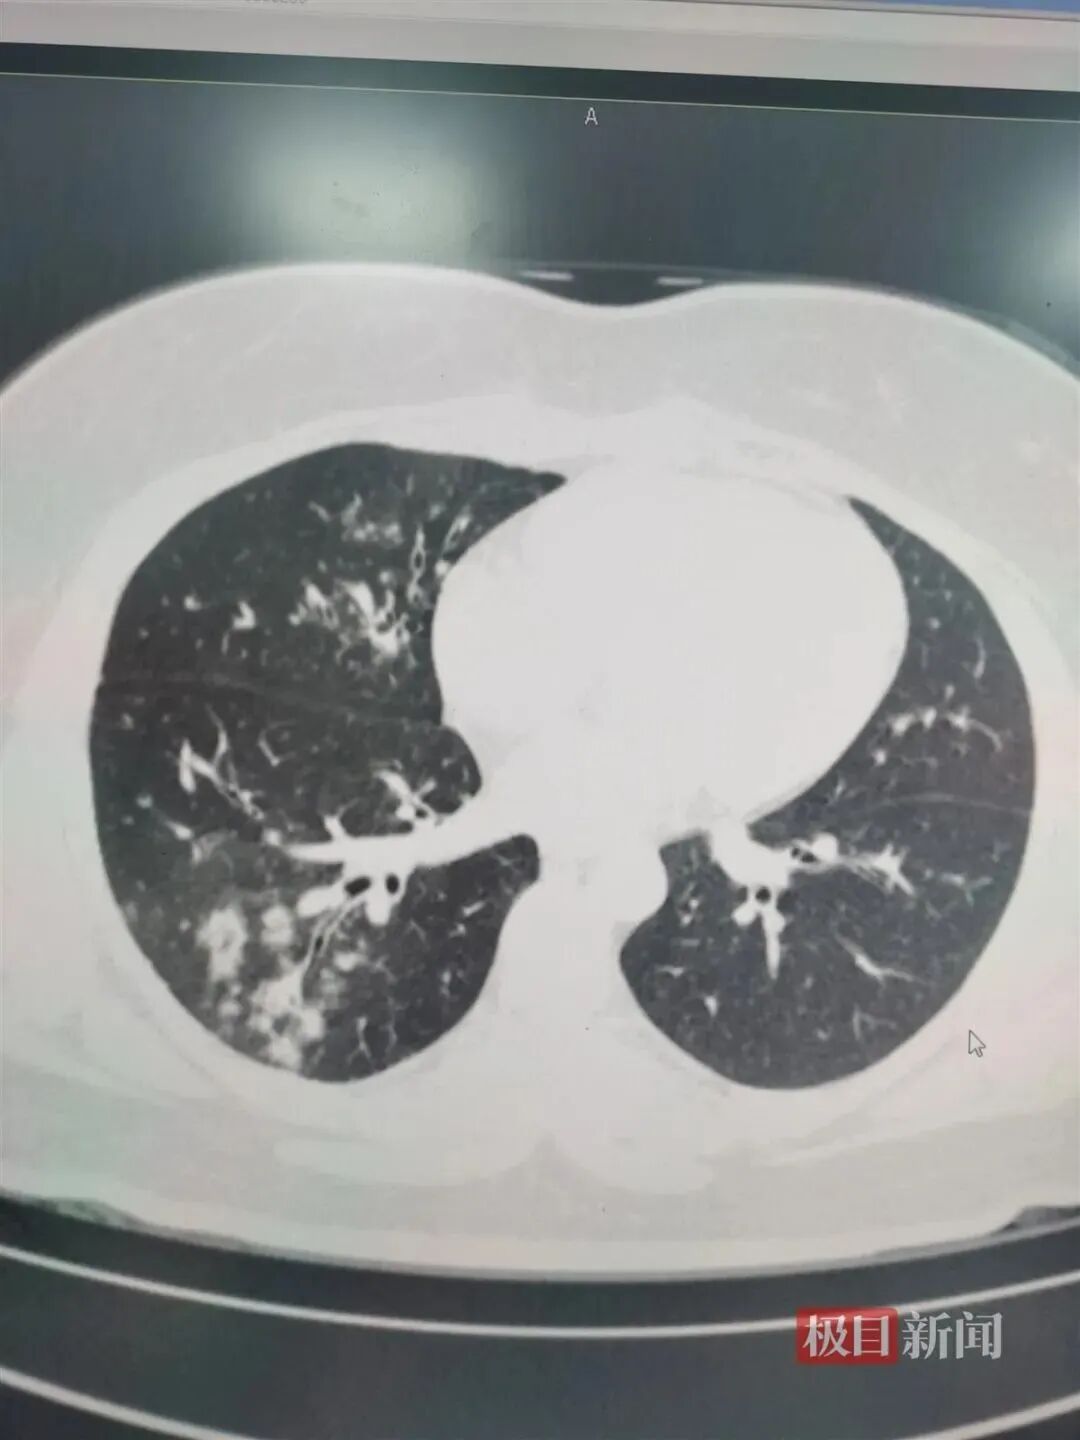

△支原体感染患者肺上呈现树雾状。

这是因为,肺炎支原体会在人体内激发出人体的免疫反应。从患者胸片,可以看到范围大小不等“白肺”的地方。

这不是说那里全是“支原体”,而主要是支原体激发出的免疫损伤、炎症浸润。

可以说,支原体肺炎是感染+免疫反应引起的肺炎。

杨澄清表示,支原体感染常引起呼吸道感染,常为咽炎、支气管炎,表现为感冒一样,部分具有自限性,部分出现顽固性的干咳,严重者可发展为肺炎甚至重症肺炎,类似小阳这样的患者,就会发展成局部“白肺”,甚至更严重的情况。